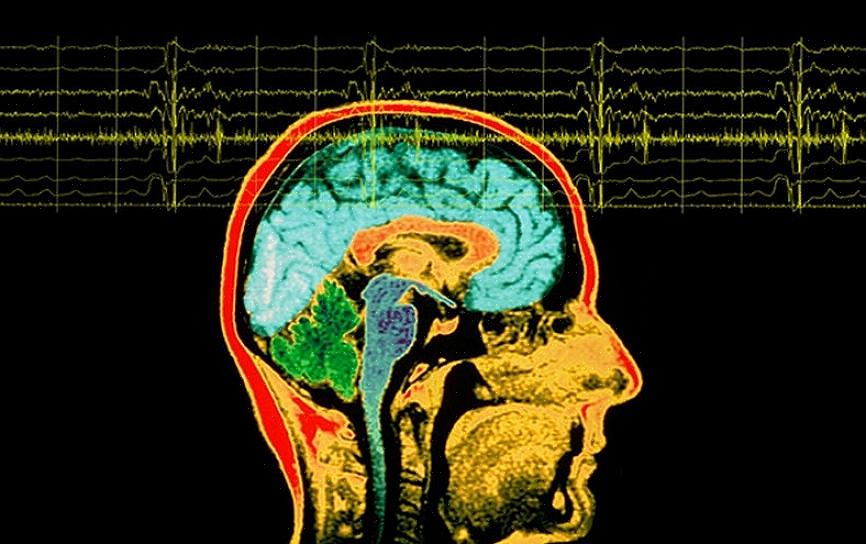

איפה האונה הטמפורלית?

האונה הטמפורלית נמצאת פחות או יותר במקום שבו נמצאות האוזניים שלך. הוא מופרד מהאונה הקודקודית על ידי הסולקוס הצידי (הידוע גם בשם הסדק הסילבי). מדענים מאמינים שזה אחד מהחלקים החדשים יותר של המוח מכיוון שרק לבעלי חוליות יש את זה.

בדומה לאזורים אחרים במוח, האונה הטמפורלית אינה מבודדת מבחינה אנטומית. זה עובד בשילוב עם כל שאר אזורי המוח. האונה הספציפית הזו היא מבנה מאוד דינמי ורגיש שנמצא באינטראקציה מתמדת עם החושים והסביבה שלך.

עובדה מעניינת אחת היא שלאונה הטמפורלית יש יותר קשרים עם המערכת הלימבית מאשר לכל אונה אחרת במוח. כתוצאה מכך, הוא אחראי למספר רב של תהליכים הקשורים לרגשות ולזיכרון.